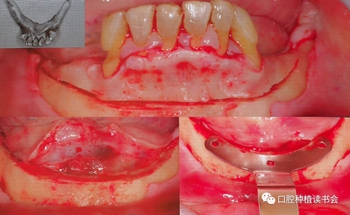

周國輝教授分享了多例精彩的Trefoil下頜無牙頜種植修復(fù)案例,我們一起分享其中一例。該患者下頜牙列缺損,余留牙松動3度,術(shù)前完成影像學(xué)檢查、排牙分析與打印3D頜骨模型,根據(jù)Trefoil的要求,種植修復(fù)體切牙切緣到骨水平的距離不應(yīng)小于22mm,為什么要保證足夠的修復(fù)空間呢?主要是因為Trefoil使用的是樹脂與金屬支架混合型修復(fù)體,而且是正式的修復(fù)體。

該患者的下頜牙槽嵴頂為刃狀,Trefoil理念的手術(shù)要求:必須修整出足夠?qū)挾鹊钠脚_,便于修復(fù)及義齒的維護,骨修整線必須兩側(cè)頦孔上方,修整后形成不小于7mm寬度的骨平臺(種植體兩側(cè)最小保留1mm骨壁)(圖6)。

圖6 下頜骨修整線,修整后安裝定位導(dǎo)板

使用超聲骨刀完成骨修整后,使用導(dǎo)板確認是否滿足種植體植入條件,然后使用球鉆定點,2mm先鋒鉆預(yù)備后,測量垂直高度,以確定是否滿足22mm修復(fù)空間的要求。在定位導(dǎo)板上,先預(yù)備中間種植窩,逐級預(yù)備,根據(jù)患者條件確認最后鉆的寬度,植入錐度連接的軟組織水平、平行壁植體,該種植系統(tǒng)是有11.5和13mm的不同長度,以及 4.5和6mm 高度的光滑頸環(huán)平行壁的軟組織水平種植體。(圖7)